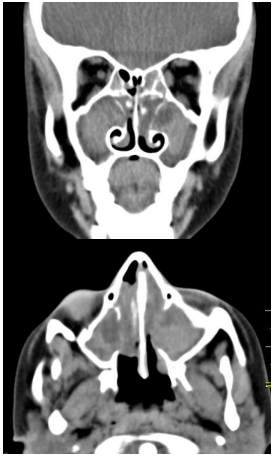

Mulher, 52 anos de idade, apresentou dor dentária há 3 meses. Na ocasião, foi submetida à extração do segundo molar superior direito, com fechamento adequado e cicatrização completa do alvéolo dentário. Desde então, evoluiu com rinorreia purulenta unilateral à direita, cacosmia e sensação de pressão facial ipsilateral. Realizou tratamento com amoxicilina-clavulanato por 14 dias, sem melhora clínica. A endoscopia nasal à direita e a tomografia de seios da face sem contraste demonstraram as imagens apresentadas a seguir:

Enunciado 4540963-1

Com base nesse quadro, qual a melhor conduta a ser adotada?